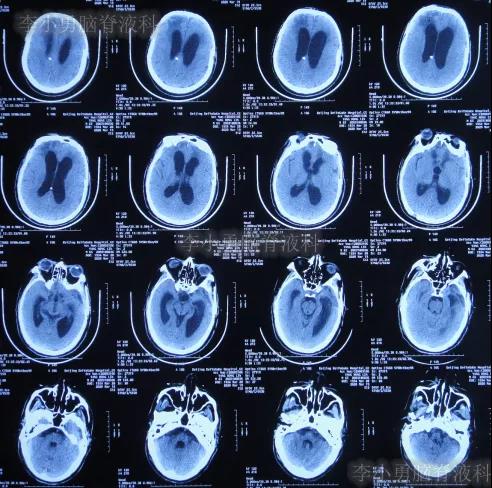

在第4家医院治疗26天,仍间断性发热、大小便失禁加重,住院期间曾2次查头颅CT(2020年2月27日(图-28)、2020年3月12日(图-29))示脑室仍扩张。

图-28:2020年2月27日头颅CT

图-29:2020年3月12日头颅CT